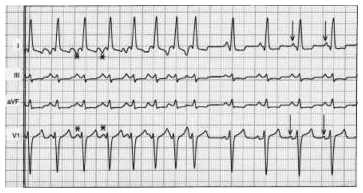

A taquicardia atrial é uma arritmia supraventricular que ocorre mais frequentemente na população pediátrica sem cardiopatia estrutural (14% das taquicardias supraventriculares neste grupo) e numa maior proporção em pacientes submetidos à correção cirúrgica de cardiopatia congênita. O eletrocardiograma de um paciente com taquicardia atrial geralmente exibe uma frequência atrial entre 120 e 200 bpm, com morfologia da onda P tipicamente diferente da onda P sinusal.

A figura representa um eletrocardiograma de um paciente com taquicardia atrial esquerda com ondas P negativas em D1 e av1, onde se observa: